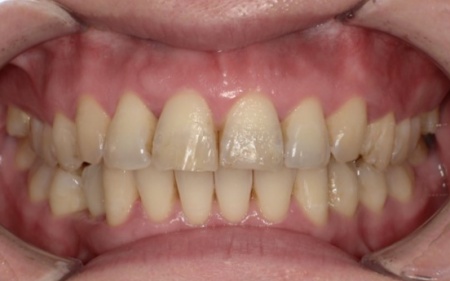

10代女性 乱れた歯並びと噛み合わせをワイヤー矯正で改善した症例

- 矯正歯科

- ワイヤー矯正

- 治療期間の目安 1年6ヶ月

- 治療費総額の目安 770,000円

・治療中、発音しにくい場合があります ・治療中、舌が動かしにくいことがあります ・治療中、装置によってまれに頬の内側が傷つき、口内炎になる場合があります ・歯の移動に伴って、違和感や痛みを感じる場合があります ・冷たいものを飲んだときに歯がしみる「知覚過敏」の症状が出る場合があります ・正...